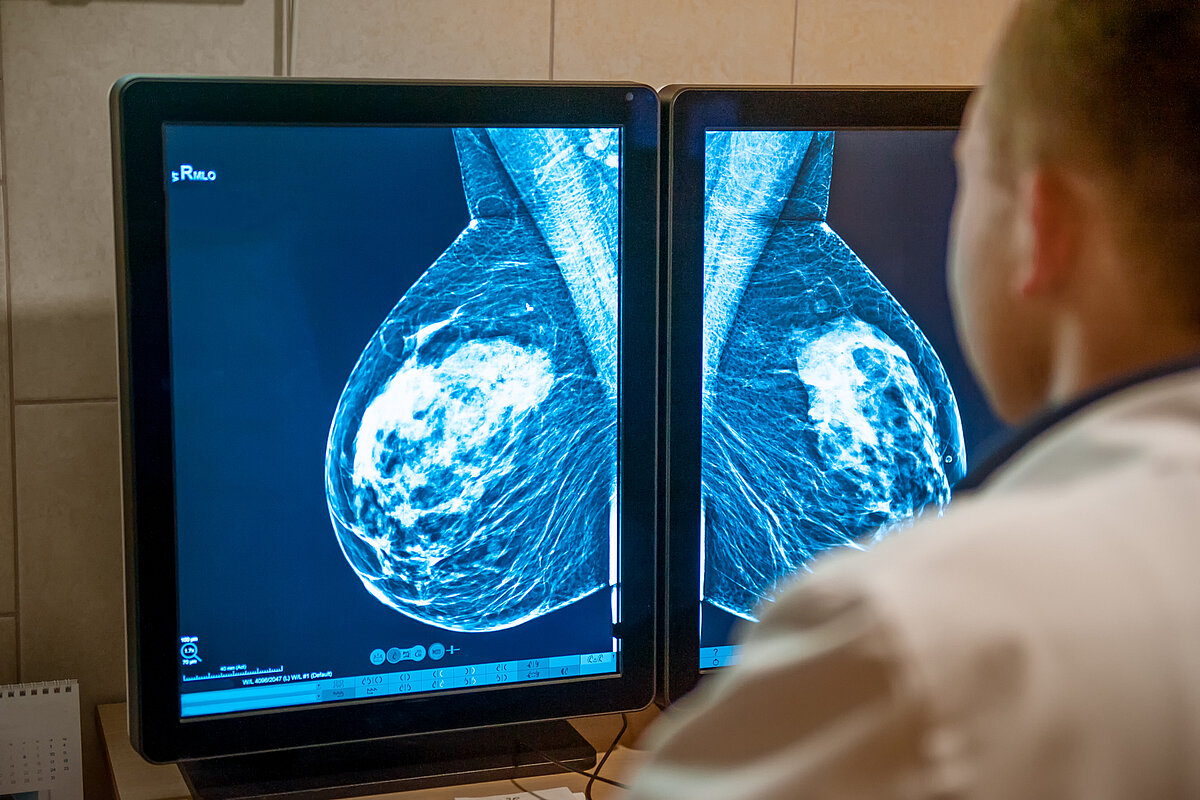

Foto: QuaMaDi: Qualitätsgesicherte Mamma-Diagnostik in Schleswig-Holstein

QuaMaDi ist ein bundesweit einmaliges, erfolgreiches Untersuchungsprogramm für Frauen mit erhöhtem Risiko oder einem Verdacht auf Brustkrebs. Zentrales Instrument ist eine strukturierte Zusammenarbeit aller beteiligten Arztgruppen (niedergelassene Gynäkologen, Radiologen, Pathologen und Ärztinnen und Ärzte in spezialisierten Brustzentren in Kliniken). Das Besondere an QuaMaDi: Jede Mammographie-Aufnahme wird nicht nur von einem, sondern zusätzlich durch einen zweiten, unabhängigen Radiologen beurteilt. Bei einem verdächtigen oder nicht eindeutigen Ergebnis begutachtet außerdem ein dritter Arzt Die ärztliche Berufsausübung, die Ausübung der Heilkunde, setzt nach der Bundesärzteordnung eine… in einem Brustzentrum die Befunde und Bilder. Der gesamte Prozess ist digitalisiert. Alle Bilder und Befunde werden auf einer zentralen telematischen Plattform - der sogenannten elektronischen Fallakte - gebündelt. Auf diese Unterlagen haben die beteiligten Ärzte einen sofortigen Zugriff.

Künftig soll die Diagnosesicherheit in QuaMaDi weiter optimiert werden: Geplant ist, nach einer Erprobungsphase unter wissenschaftlicher Begleitung ein spezielles KI-Programm einzusetzen, das die Radiologen bei der Befundung der Mammographie-Aufnahmen unterstützt. Ziel ist, dass sich der sogenannte Zweitbefunder auf die komplexen und dringlichen Fälle konzentrieren kann und dabei nichts übersieht.